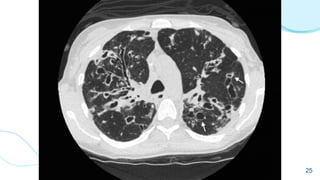

ACHADOS

RADIOLÓGI

COS

➔ Diâmetro brônquico aumentado

(sinal do anel de sinete);

➔ Sinal do trilho do trem;

➔ Brônquios visíveis nas periferias

pulmonares;

➔ Brônquios não afilam

progressivamente;

➔ Impactação mucoide;

24

focal

afetando muitas áreas dos

pulmões

aparecendo em apenas 1 ou

2 áreas pulmonares

difusas

ACHADOS RADIOLÓGI COS ➔ Diâmetro brônquicoaumentado (sinal do anel de sinete); ➔ Sinal do trilho do trem; ➔ Brônquios visíveis nas periferias pulmonares; ➔ Brônquios não afilam progressivamente; ➔ Impactação mucoide; 24

focal afetando muitas áreasdos pulmões aparecendo em apenas 1 ou 2 áreas pulmonares difusas 25